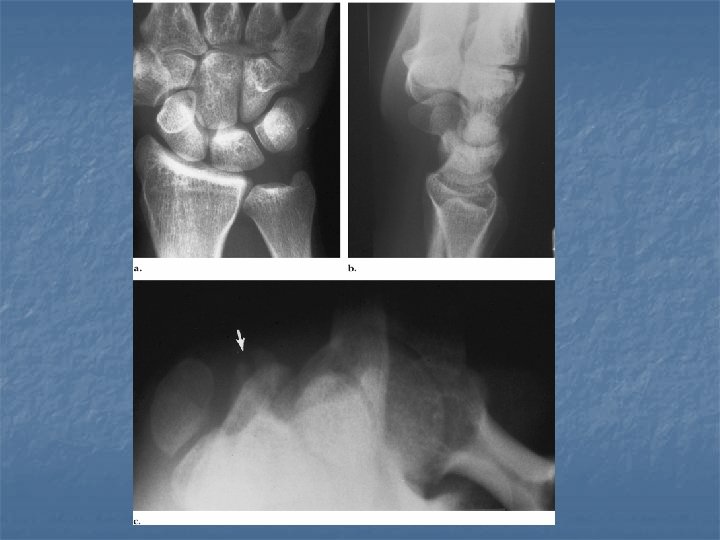

Perilunate dislocation n On lateral view: Dorsal or volar dislocation of the capitate. n Lunate remains in articulation with the radius although there may be some degree of tilt n n On dorsovolar view Crowdening of the proximal and distal carpal rows n Break in arcs II and III at the site of the capitate n

Lunate dislocation n On lateral view Axis of lunate is titled away from the articular surface of radius (spilled tea cup sign) n Capitate remains in normal alignment with radius and 3 rd metacarpal n n On dorsovolar view n Disruption of arc II while arc III remains intact